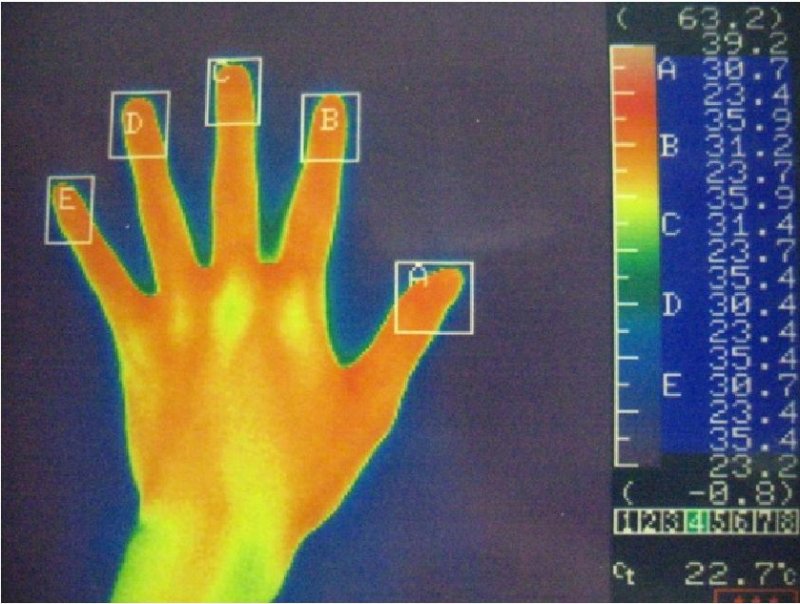

サーモグラフィー

左手

右手

赤い部分が高温部位を示しています。

左手

右手

明らかに両手の体温の低下がみられ、術直後から多汗症の症状は消失します。